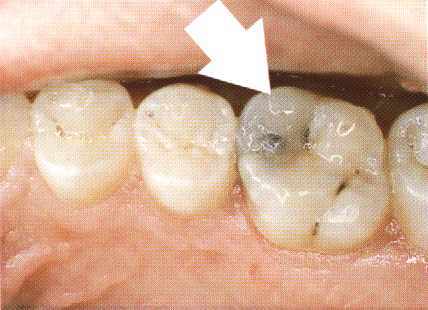

Een amalgaamvulling versterkt de kies niet. Daardoor is aan de tongzijde de knobbel van de kies afgebroken naast de vulling.

De hele vulling is verwijderd en met composiet is de kies hersteld.